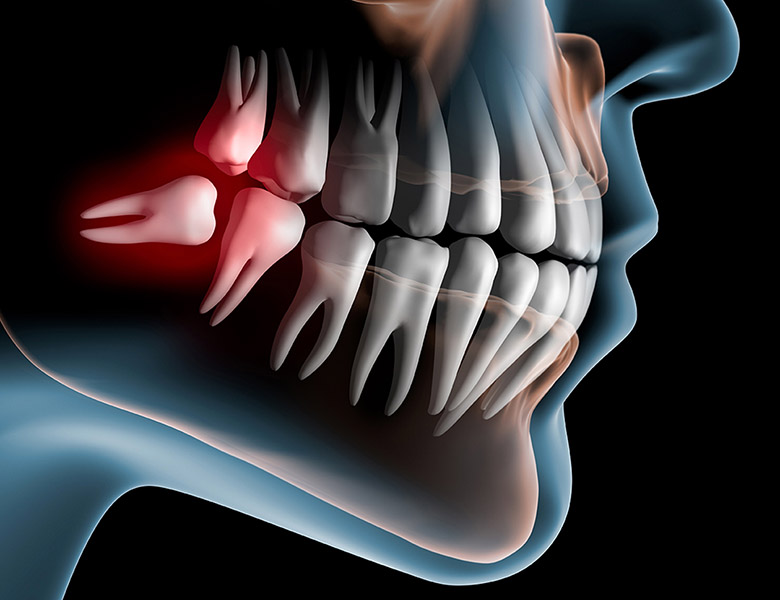

親知らずの抜歯

親知らずのトラブルは、痛みや腫れだけでなく、手前の健康な歯を虫歯にしたり、歯並びを悪くしたりする原因になります。

当院では、口腔外科医としての熟練したテクニックにより、手術時間を短縮。

組織へのダメージを抑えることで、術後の痛みや腫れを軽減させるよう努めています。